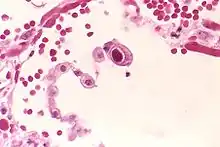

CMV infection can be demonstrated microscopically by the detection of intranuclear inclusion bodies. On H&E staining, the inclusion bodies stain dark pink and are called "owl's eye" inclusion bodies.[45]

Lytically replicating viruses disrupt the cytoskeleton, causing massive cell enlargement, which is the source of the virus' name.